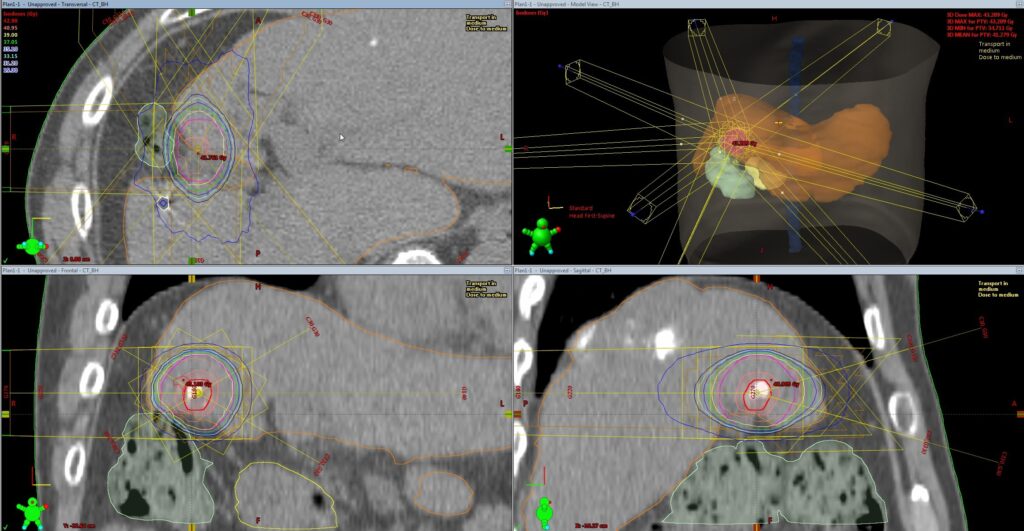

転移がない比較的早期の癌に対する治療の第一選択は、多くの場合、手術となっています。一方で近年、放射線治療の技術、機器が発達し、腫瘍に対してピンポイントで高線量の放射線を投与する「定位放射線治療」を一般病院でも行うことができるようになりました。この方法により、早期肺癌や肝臓癌などにおいて、高齢者等に対しても安全に根治治療を行うことが可能となりました。当院においても80歳を超える方や、合併症によって手術の負担に耐えられないような方に対し、定位放射線治療を比較的安全に行うことができています。治療効果に関しても、手術に近い結果が、近年多数報告されています。

加えて、当院には県内で唯一(2021年4月時点)となる動体追跡システムが導入されています。肺や肝臓などの臓器は呼吸に伴って1cmから2cm程度の上下動を繰り返しています。そのため、ピンポイントの放射線治療を行う際の精度が落ちる可能性があったり、放射線を当てる範囲を大きくしたりする必要があります。治療を行う際、このシステムを使用することで、腫瘍近傍の肺や肝臓の動きをリアルタイムに観測することができ、腫瘍が特定の位置に来た時のみ、放射線を当てることが可能となります。そのため、照射範囲を縮小し、よりピンポイントに、より安全に治療を行うことが可能です。動体追跡を用いた治療を行う際には事前に金製のマーカーを腫瘍近傍に挿入する必要がありますが、そういった処置が可能な場合、当院では積極的に動体追跡を併用した定位放射線治療を行なっています。安全性の問題から動体追跡を併用した方が望ましい場合、新潟市や長岡市などの他の医療圏からの紹介で治療を行うこともあります。現在、当院では早期肺癌や肝臓癌に限定して動体追跡放射線治療を行なっております。対象となる方でご興味をお持ちの方は一度ご相談ください。